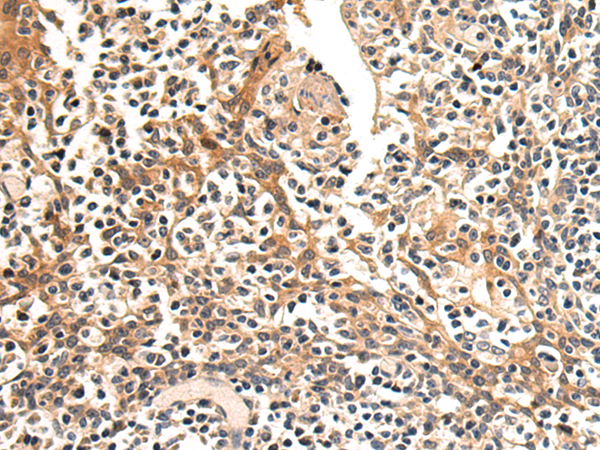

分类: 科研抗体货号: P04879别名: ATOD2应用: IHC反应种属: Human